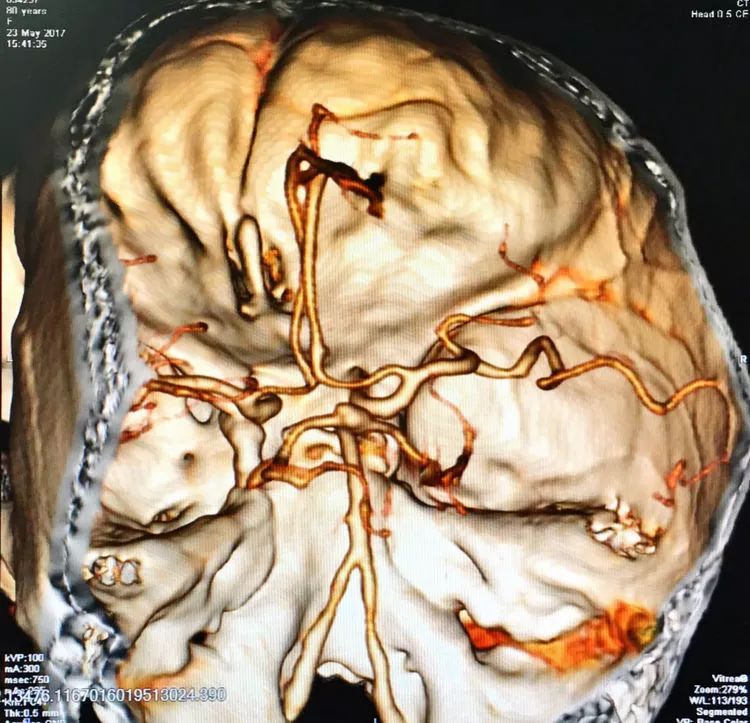

患者女性,80岁,以SAH于2017.5.20急诊入院,CTA示基底动脉顶端动脉瘤。

左椎动脉造影三维重建和测量

回头再观察左椎动脉造影的三维成像,发现瘤腔确实有向后方突出的分叶,明确弹簧圈团后部的空虚处仍是瘤腔的一部分